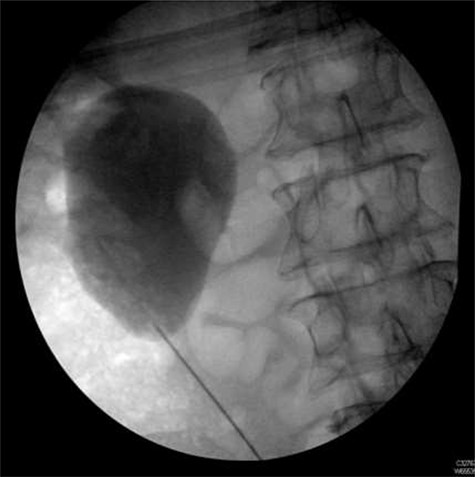

Seven months after the patient’s initial presentation, they underwent a laparoscopic right hemicolectomy; intra-operatively, a 6Ch/24 cm stent was inserted into the right ureter by the colorectal surgeon who had good experience of ureteric stent placement. The position of the stent was confirmed with cystoscopy and retrograde pyeloureterogram (Fig. 2).

Retrograde pyeloureterogram confirming position of right ureteric stent.